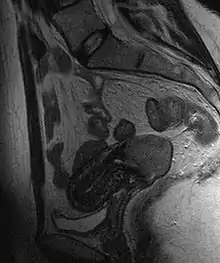

Often before the biopsy, the doctor asks for medical imaging to rule out other causes of woman's symptoms. Imaging modalities such as ultrasound, CT scan, and MRI have been used to look for alternating disease, spread of the tumor, and effect on adjacent structures. Typically, they appear as heterogeneous mass on the cervix.[53]

Invasive squamous cell carcinoma of the cervix is characterized by infiltration as irregular anastomosing nests or single cells.[64] This case is poorly differentiated. H&E stain.